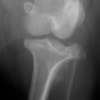

左後肢の挙上を主訴に来院されました。触診にて両関節の前方引き出し兆候、両膝蓋骨の内方脱臼を認めました。関節液検査より免疫介在性多発性関節炎は否定的でした。レントゲン検査にてfat pad signを伴う関節炎が認められたことから、前十字靭帯断裂と膝蓋骨内方脱臼(左GradeⅢ 右GradeⅢ〜IV)併発と診断し、手術を行いました。

手術は片足ずつ行い、両膝とも術中の関節鏡検査にて前十字靭帯の完全断裂と半月板損傷を確認しました。TPLO、半月板切除と滑車溝形成を始めとした膝蓋骨脱臼整復術を実施いたしました。膝蓋骨の安定化を測るために外側支帯を強固に縫合し、内側支帯は切除し縫合せずに開放状態にしています。

術後の歩行状態は良好です。

術前のTPAは左後肢33.1°右後肢26.8°でしたがTPLO実施により左後肢5.5°右後肢12°に矯正されました。

術前左後肢側面像

術前正面像

術後左後肢側面像

術後左後肢正面像